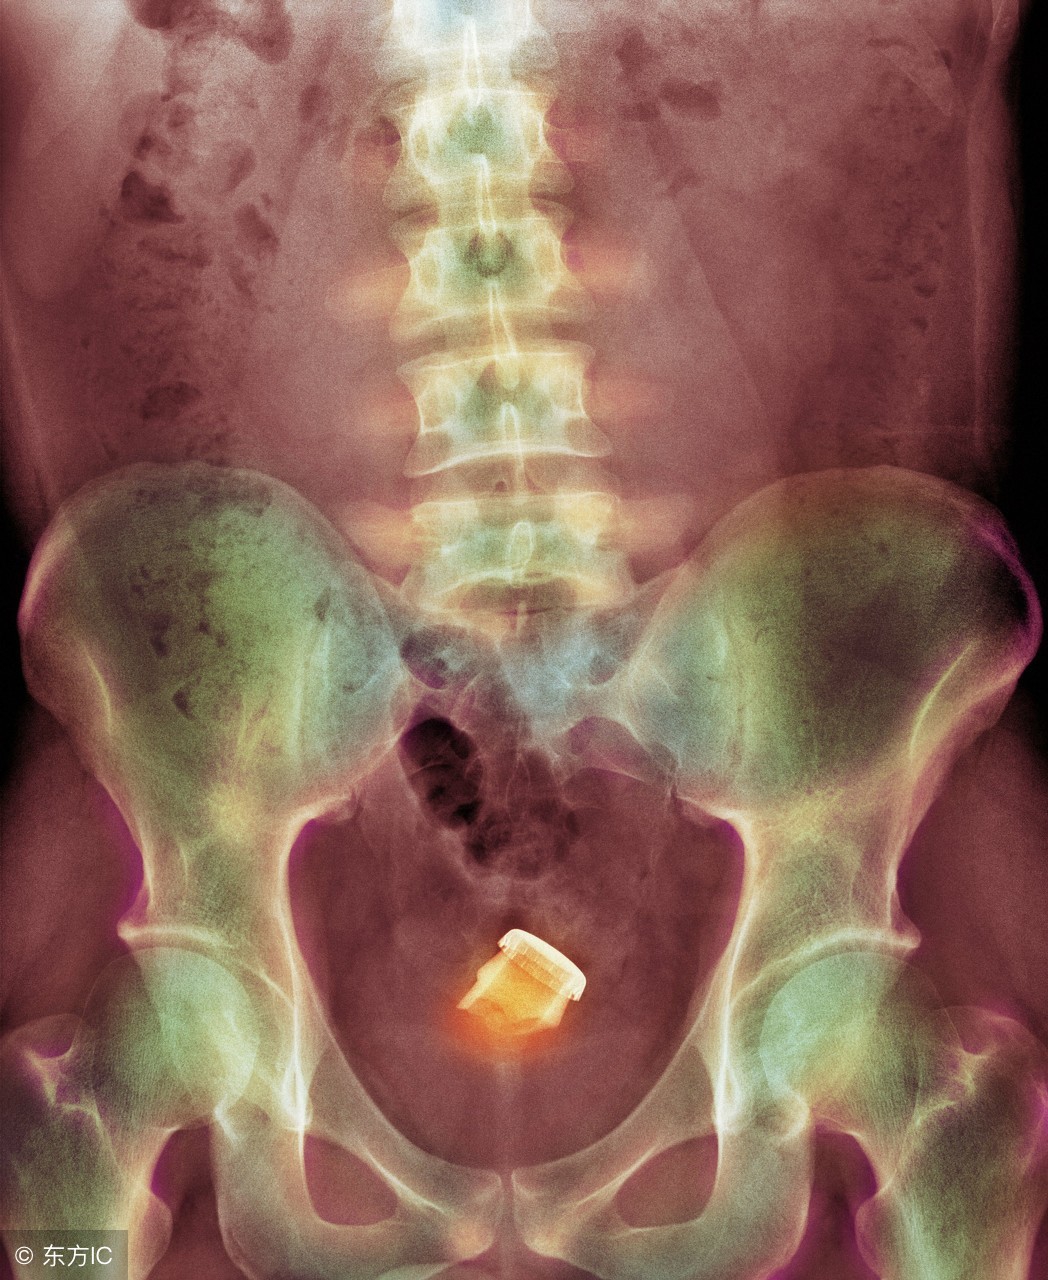

最近急诊科住了一名患者,因为直肠内异物被收治入院。直肠异物并不算什么罕见的事情,只不过这次的异物有点特殊:是个灯泡。

患者是个四十多岁的男性,由于各种原因,不慎将灯泡塞入体内无法取出。后因担心灯泡在体内破裂,故来就医。

不管什么时候,只要提到直肠异物的问题,大家难免带着猎奇的心态去看待。不论什么原因,都会觉得是借口。因为涉及病人隐私,关于灯泡如何进入体内的方式我们不做过多讨论,现在讲一下如何把异物取出。